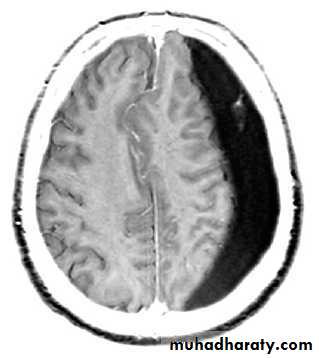

A 65 year old man is brought to the Emergency Department as he has had a fit. He is slow to regain consciousness and so has a brain scan. He has had no known history of trauma.

Your answer

Correct answera.

Extradural haematoma

b.

Normal scan

c.

Subdural haematoma

d.

Glioma

• What is the most likely diagnosis?

•a : Extradural haematoma

You would expect to see a convex shaped lesion in a patient with an extradural haematoma.b : Normal scan

This scan is abnormal.

c : Subdural haematoma

This cross section image of the brain is from a person who sustained a head injury. The injury resulted in bleeding beneath the dura mater. This is a subdural haematoma. Patients may have no history of trauma.

d : Glioma

This is not a glioma.